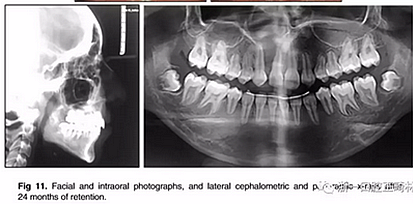

治療持續(xù)3年,患者始終保持積極和合作。口腔衛(wèi)生很好。患者和她的父母都對結(jié)果感到滿意。經(jīng)過24個月的保持后,咬合保持得很好(圖11 ; 圖12)。在上牙弓中,應(yīng)用固定舌側(cè)保持器以防止任何復(fù)發(fā)傾向。在下牙弓中,治療后拔除第三磨牙。